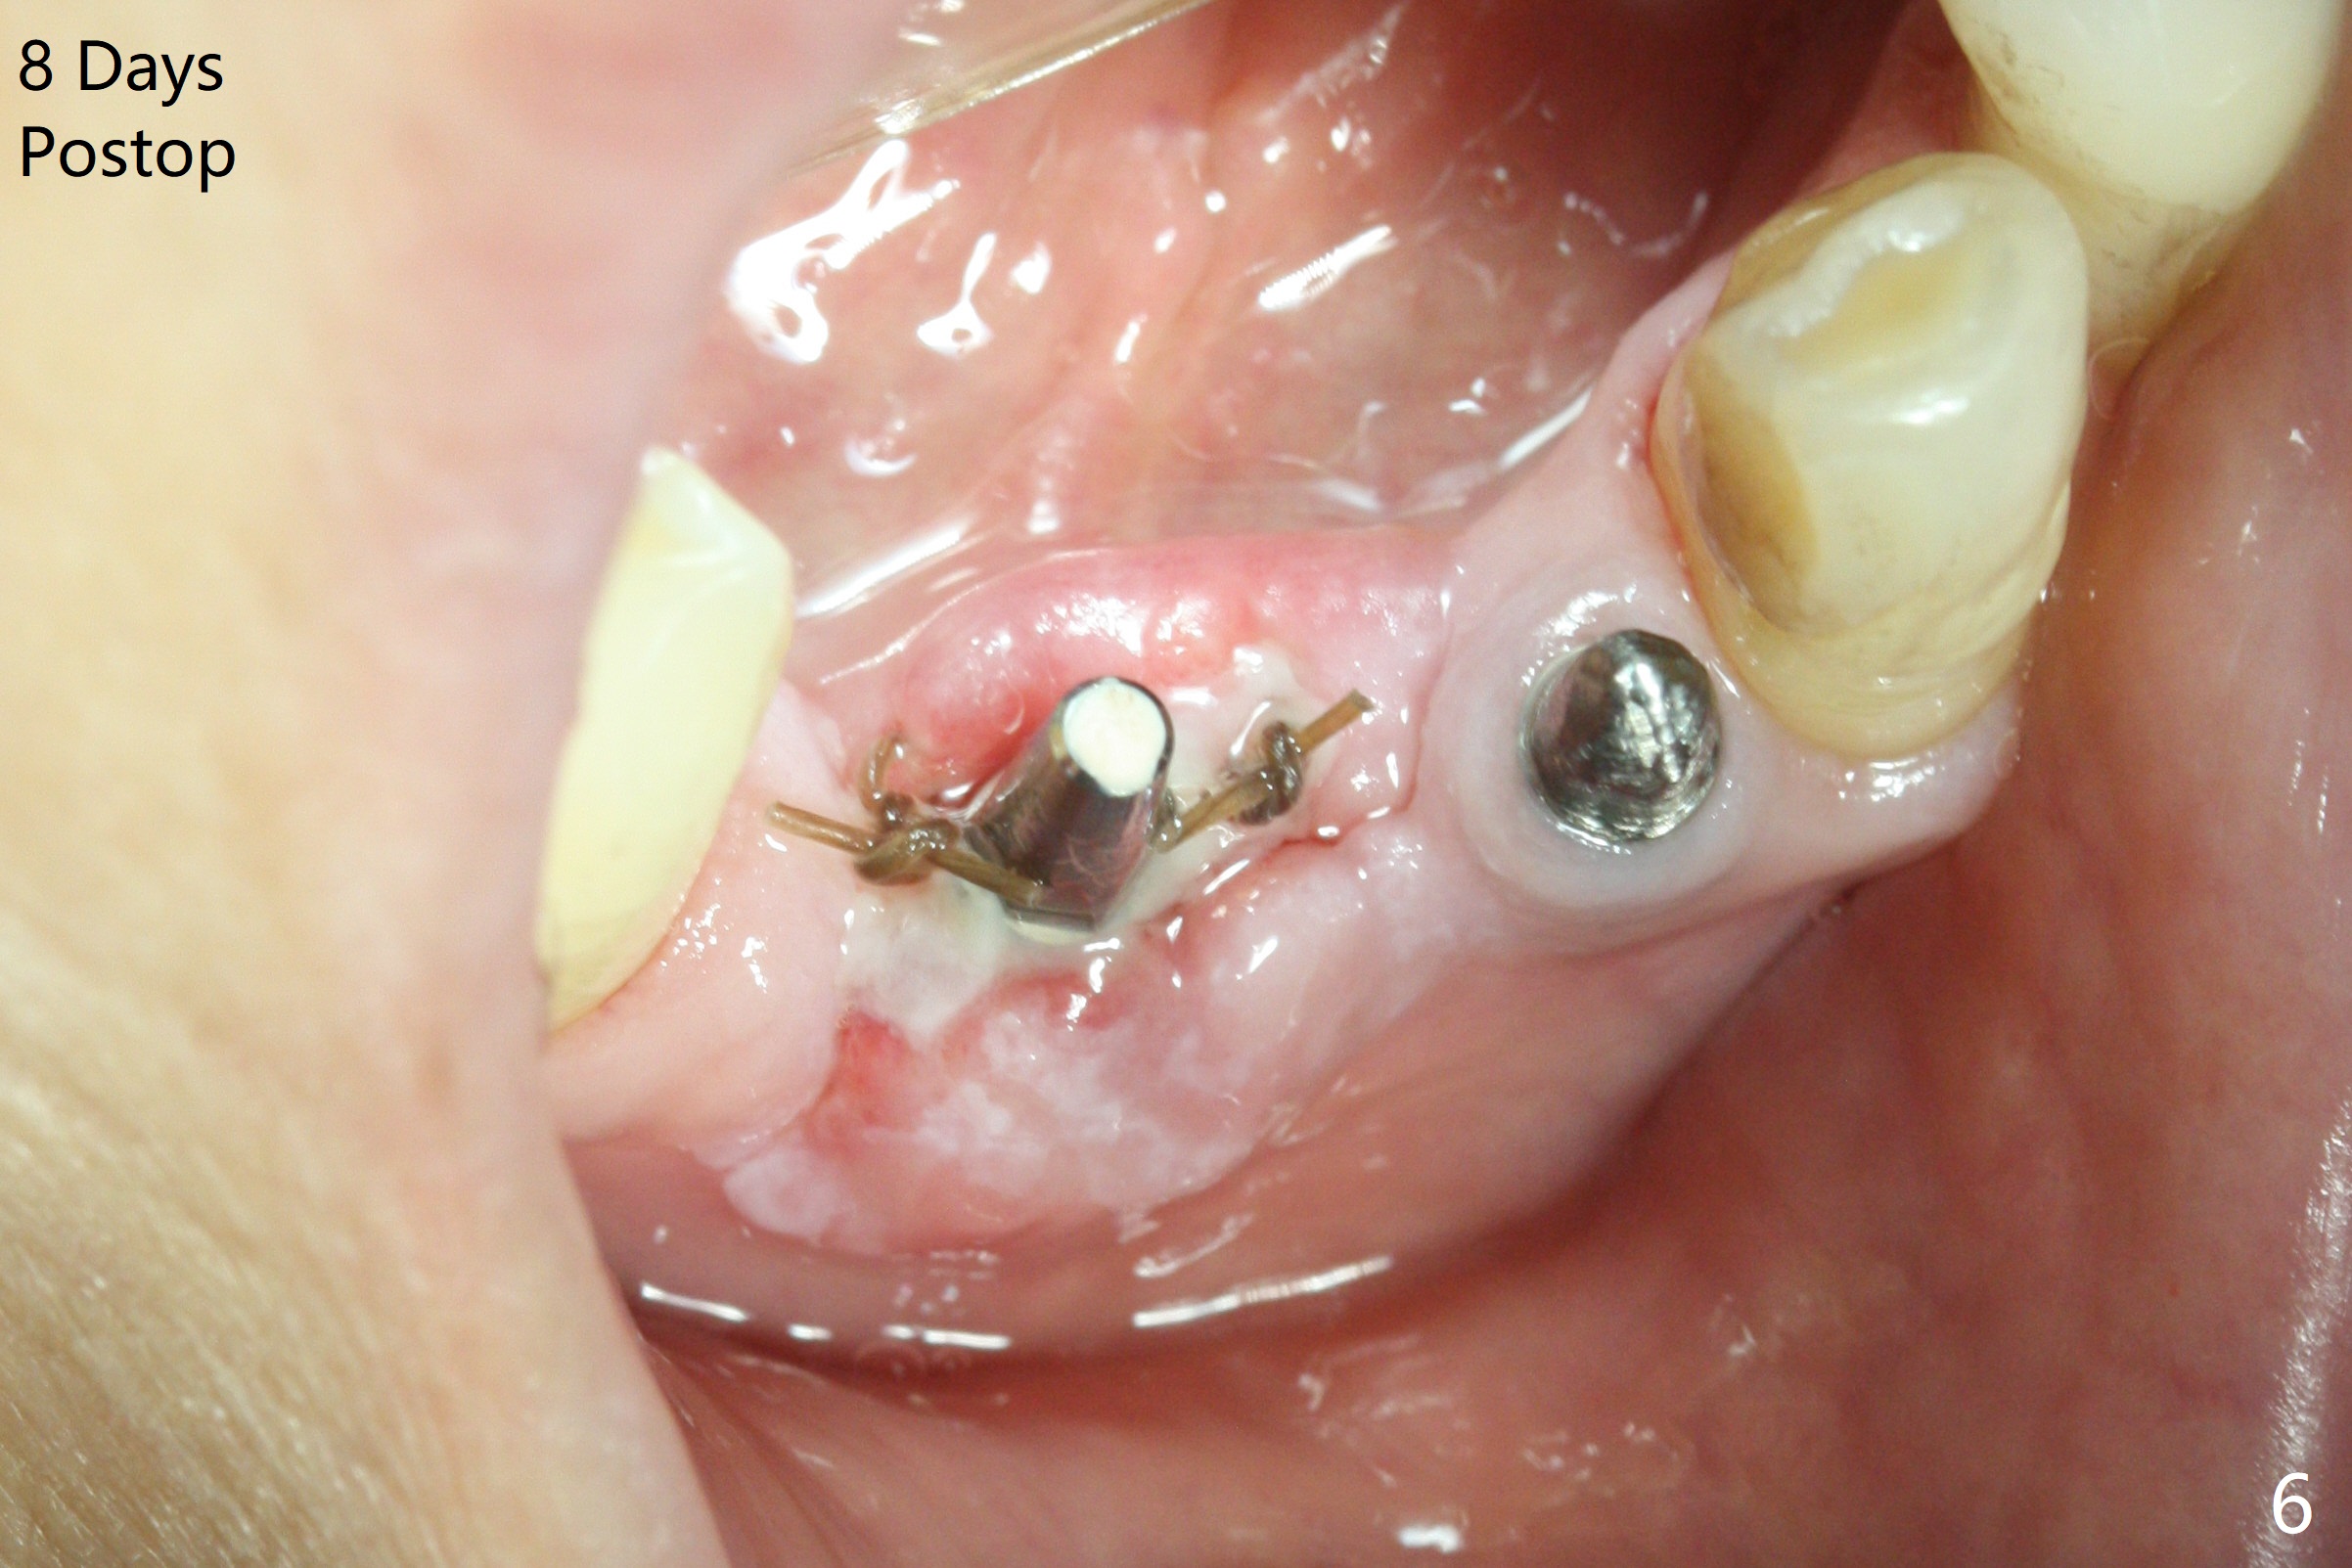

After removing #23-26 FPD and the 3x14 mm 1-piece implant at #26 (Fig.1,2 *), a new osteotomy is initiated in the narrow ridge (after ridge top reduction) approximately at #25 (Fig.2 <). Following placement a 2x10(4) mm implant at #25 (Fig.3-5) and Osteogen plug in the osteotomy at #26, Vanilla graft is placed around the implant, especially buccal. Periodontal dressing is applied after suturing. The buccal and lingual flaps are erythermatous and edematous without pain 8 days postop (Fig.6). The wound seems to be healing 2 weeks postop (Fig.7), no sign of osteonecrosis. With placement of a 2 mm implant at #25 (Fig.8 (>: bone graft buccally)), the buccal plate remains normal in thickness. When a 3 mm implant is placed at #23 (Fig.9), approximately 4 threads appear to be exposed (between arrowheads), partially due to the thick lingual plate (*).